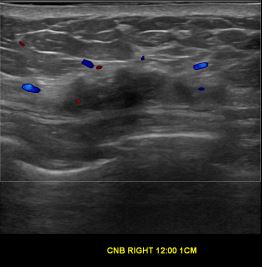

상기환자는 우측 유방 유두 분비물있어  내원하신 40대후반 여성분으로 의심스러운 우측혹 조직검사 시행해 유방암으로 진단되었습니다